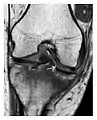

Fatigue fractures

Fatigue fractures occur when healthy bone is exposed to repeated stress. The bone is a living tissue, with the capacity to repair itself; fatigue fractures occur when repetitive injuries exceed the repair capacity of the bone. This type of fracture does not occur as a single event but rather incrementally as a sequence of cellular events that begin with increased osteoclastic activity. Microfractures occur later and are accompanied by bone marrow edema, which can be detected on MRI. This stage appears on MRI as an isolated bone marrow edema pattern without a fracture line and is called stress reaction. Then, periosteal new bone forms and may be visible on radiography. Full cortical fractures occur if the repetitive stress continues. Only timely detection and appropriate management can interrupt this sequence.[1]

Fatigue fractures are more frequent in women which may be due to the relatively smaller bones of women. Moreover, pregnancy is a well-recognized risk factor for femoral neck fatigue fracture. While fibular and metatarsal fractures have a low risk of complications, other sites including the femoral neck, midanterior tibia, navicular, talar, and other intraarticular fractures are prone to complications such as delayed union, nonunion, and displacement. The site of the insufficiency fracture may be specific to the activity: for example, rugby and basketball players are more prone to navicular fractures, while gymnasts have a higher risk for talar fractures (Figure 7). Long distance runners are at increased risk for pelvic, tibial (Figures 8 and 9), and fibular fractures. In the military, calcaneus (Figure 10) and metatarsals are the most commonly cited injuries, especially in new recruits. Billiard players are at risk for upper limb fractures (Figure 11).[1]

a

b

Figure 7: Fatigue fracture of the talus in a 25-year-old male basketball player with right hind foot and ankle pain, without history of trauma, and a normal initial radiograph (not shown). (a) One-month followup lateral radiograph shows normal appearance. (b) Sagittal T1-weighted MRI shows an irregular fracture line (arrow) within an ill-defined area of hypointensity corresponding to bone marrow edema.[1]